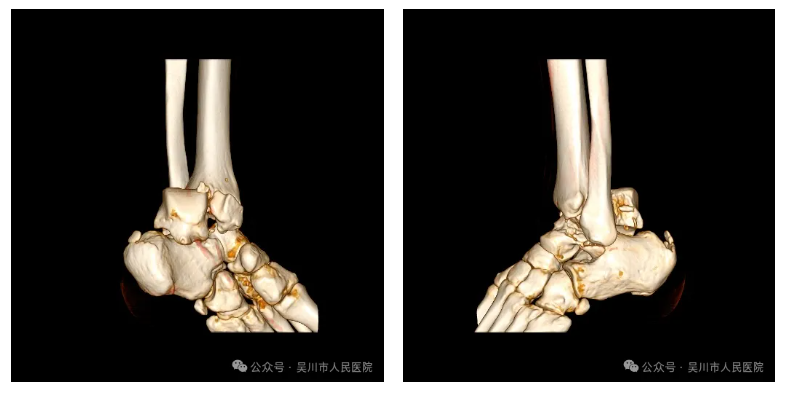

患者一周前因意外导致左踝部严重受伤。送入我院时,患者的左踝已严重肿胀变形。CT提示左侧内踝骨折、距骨粉碎性骨折合并脱位,关节面损伤,脆弱的血管神经束受到碎裂骨块的压迫。

足踝部位血供特殊,此类严重骨折不仅破坏骨骼结构,危及软组织血运。若不妥善处理,患者可能面临距骨坏死、足踝功能永久性受损的风险。

面对复杂病情,在广东省中医院陈海云教授的指导下,我院骨外科一区联合医学影像科,利用三维重建技术进行多次术前模拟推演,最终确定了“有限切开结合微创内固定”的方案。

手术过程中,手术团队运用直径仅2毫米的导针,在狭窄的骨缝间小心翼翼地穿行,将塌陷的关节面逐一复位,再用中空螺钉稳稳固定核心结构,全程借助术中透视技术,确保每一枚螺钉的位置、深度都恰到好处,既实现了牢固固定,又完美避开了周围的血管神经。历时3小时,成功完成了这场高难度的“骨骼修复工程”。